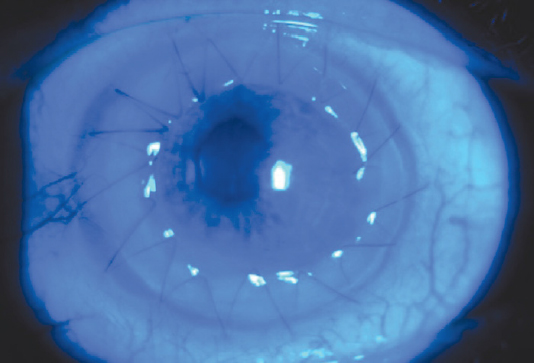

Female patient H., 79 years old, was admitted to the Research Institute of Eye Diseases with a diagnosis: “right eye – condition after automated endothelial keratoplasty with Descemet’s membrane removal (DSAEK), left eye – Fuchs endothelial dystrophy, both eyes – high myopia, and pseudophakia. On admission, visual acuity of the right eye was 0.5 incorrigible, whereas that of the left eye was 0.01 incorrigible. Intraocular pressure at all stages was within normal limits. Taking into consideration fibrotic changes in the cornea against the background of chronic corneal edema in the left eye, SPK according to the traditional method was performed. In the postoperative period, the patient received standard therapy. On day 15, epithelialization of the graft was absent (Fig. 2). Voluntary informed consent was obtained from the patient for further treatment. Additional therapy was performed against the standard therapy and included daily instillation of eye drops of autologous PRP lysate 4–5 times a day. Complete epithelialization of the graft was recorded on the postoperative day 35 (Fig. 3). The therapy lasted 3 weeks.

Fig. 2. Before treatment start, Day 15 after surgery

Рис. 2. До начала лечения, 15-е сутки после операции

Fig. 3. After treatment with platelet-rich plasma lysate, Day 35 after surgery

Рис. 3. После лечения, 35-е сутки после операции лизатом обогащённой тромбоцитами плазмы

Control examinations were performed after 3, 6, 12, 18 months. There was no PED recurrence observed. In 6 months after surgery, visual acuity was 0.25 incorrigible, after 12 months, it was 0.3 with a pinhole aperture.